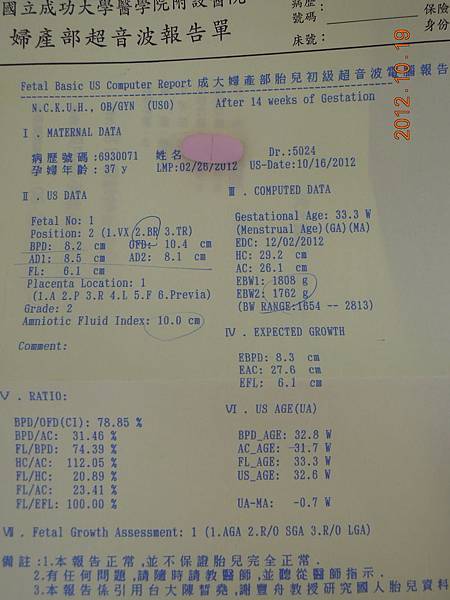

今天我們來到嘉義市博物館 ,準備看這個有趣的展覽~~ 又到了寶包體檢大考驗的日子了!!

又到了寶包體檢大考驗的日子了!! 這張也太high了吧!!